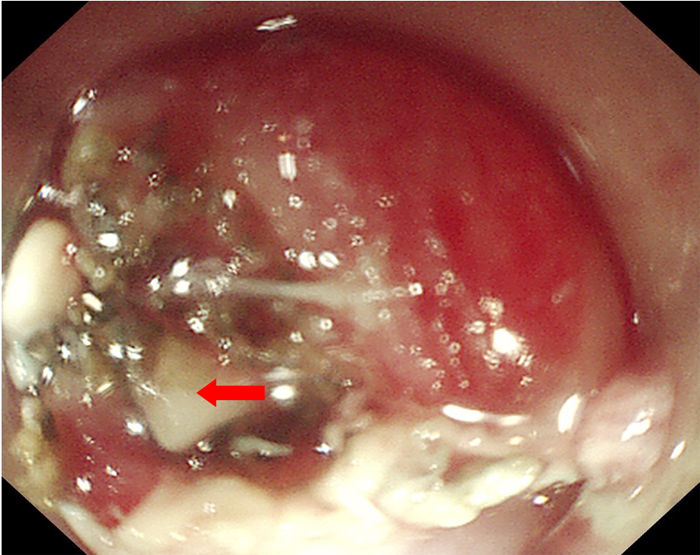

為了解魚刺與周圍的關(guān)系及是否刺入血管,患者入院后給予完善胸部強化CT,示胸上段管腔內(nèi)高密度影,考慮食管異物。李曙暉主任醫(yī)師結(jié)合患者病史、2次胃鏡結(jié)果及胸部CT等,分析認為魚刺已深深扎入食管壁內(nèi),可行食管黏膜剝離術(shù)暴露出異物后再行取出。12月28日,李曙暉主任醫(yī)師在麻醉和護理團隊的配合下行胃鏡檢查,內(nèi)鏡下距門齒18cm可見食管黏膜充血水腫,未見異物,遂用黏膜切開刀切開周圍黏膜及肌層,暴露出異物頂端,再用鱷口鉗鉗住魚刺頂端,順利取出一枚長3cm多的魚刺,看到大部分魚刺扎入食管壁。術(shù)后對癥治療后,患者現(xiàn)已痊愈出院。

食管黏膜及肌層剝離后看到露出的魚刺